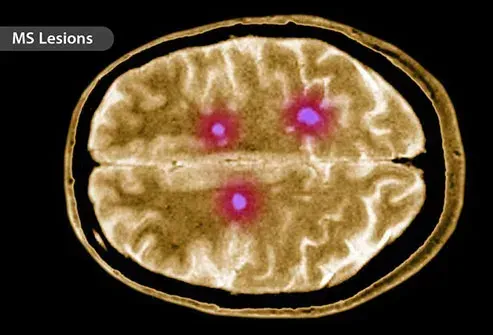

Sclérose en plaques

Lorsque vous avez une SP, votre système immunitaire attaque les nerfs de votre cerveau et de votre moelle épinière. Votre corps envoie des globules blancs pour nuire à la myéline la couche d'isolation autour des nerfs. Cela provoque des lésions nerveuses et perturbe le flux d'informations vers et depuis le cerveau. Au fil du temps, le tissu cicatriciel se forme sur les nerfs et crée des lésions. Ces changements conduisent à des choses comme les tremblements d'engourdissements et les problèmes de vision.